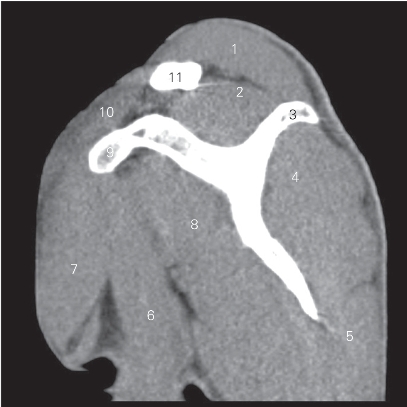

图4-3 经肩关节的矢状断层CT图像(软组织窗)

1 肩峰 acromion 2 肩胛冈spine of scapula

3 冈上肌 supraspinatus 4 关节盂 glenoid cavity

5 冈下肌 infraspinatus 6 小圆肌 teres minor

7 大圆肌 teres major 8 肱骨体 shaft of humerus

9 肱二头肌 biceps brachii 10 肩关节 shoulder joint

11 肱骨头 head of humerus